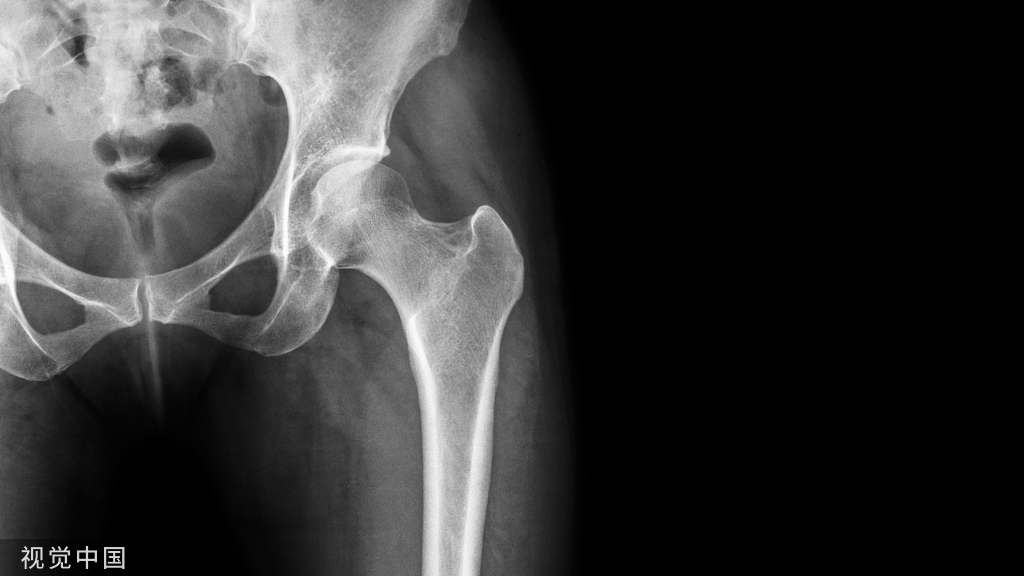

股骨颈骨折术后康复锻炼(1)骨折复位固定后即可早期做趾与踝关节的主动伸屈、旋转活动练习,股四头肌静止收缩,每天3-4 次,每次 10 下。(图 17)。

(2)术后第二周开始在保持股骨不旋转、不内收情况下做髋与膝关节主动屈伸活动。(图18)

(3)3周后可主动做屈伸患肢练习,方法是坐在床边,小腿下垂,双脚踩地或脚蹬地,练习用双臂撑起上身和抬起臀部。(图 19)

(4)在骨折恢复期,术后 1个月要加强髋、膝、踝部的肌力,以恢复行走能力,加强下肢的稳定性。主要方法是进行坐位与站位转换活动练习,以锻炼髋关节;踝关节主动屈伸、旋转活动,以及下蹲起立。(图20、图 21)

股骨干骨折术后功能锻炼(1)骨折早期,做下肢股四头肌静止收缩,踝关节伸屈活动。(见图17)

(2)4周后可以练习坐在床边进行髋、膝、踝部的主动运动(锻炼方法同股骨颈骨折)。